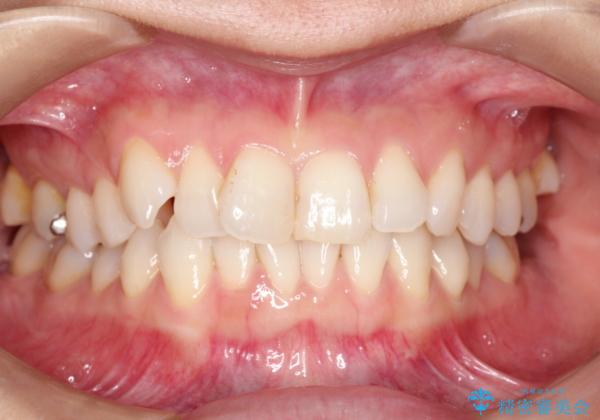

八重歯と前歯のガタガタをインビザラインで

- 八重歯と前歯のガタガタを主訴に来院されました。

目立たず矯正したいとのことでインビザラインで矯正することとしました。

インビザラインで目立たずに治療を終えることができ、喜んでいただけました。